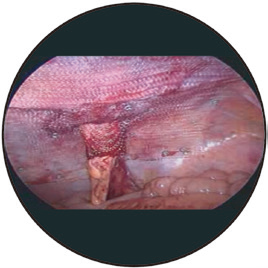

適應(yīng)癥:適用于造口旁疝的預(yù)防和治療,腹腔鏡手術(shù)和開(kāi)放性的外科手術(shù)中均可應(yīng)用。

■獨(dú)一無(wú)二的3D袖口設(shè)計(jì),依靠編織技術(shù),無(wú)縫連接,是化平面為立體的卓越產(chǎn)品,保證術(shù)后復(fù)發(fā)率最低。

■獨(dú)特的編織技術(shù),平片部分可以任意裁剪,彈性的袖口具有不同的大小(2,3 cm若剪開(kāi)袖口須術(shù)中重新縫合),滿足不同直徑的回腸造口及結(jié)腸造口的需要,亦避免了補(bǔ)片可能對(duì)腸腔造成的侵蝕。